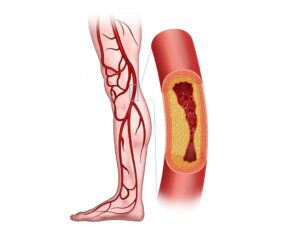

Best Dialysis Service Hospital in Madurai

Preethi Hospitals is recognized as the Best Dialysis Service Hospital in Madurai, offering advanced renal care with precision, compassion, and consistency. As the Best Dialysis Service Hospital in Madurai, we